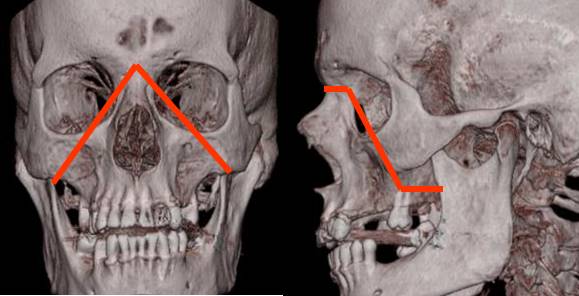

Fig 223. Diagrama de Lefort II.

Fractura en forma piramidal, con ápex en la sutura nasofrontal y base en los dientes.

Compromete el borde interno, piso de la órbita y el hueso malar.

Fig 224. Lefort II.

A: TAC axial. Fractura de la lámina pterigoidea y el piso de la órbita derecha.

B: TAC reconstrucción coronal. Fractura no desplazada de la órbita. Adicionalmente hay fractura de la pirámide nasal derecha. (Flecha gruesa).